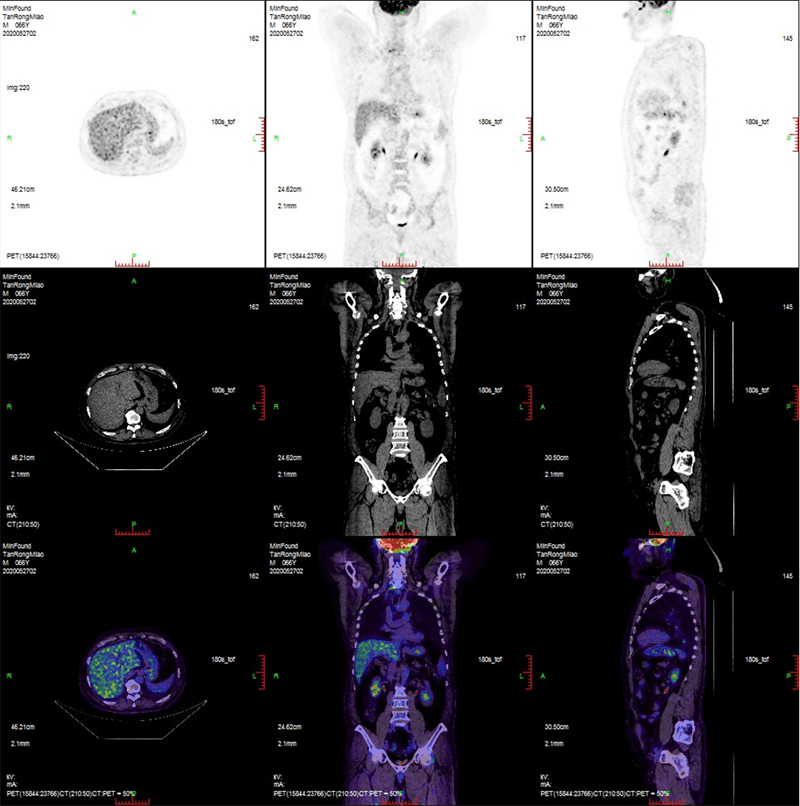

臨床畫廊